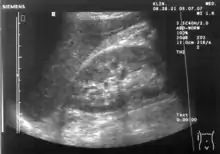

Ultrasound of liver (left side of the image) and right kidney (right side of the image) and Morison's pouch, not containing fluid.

Ultrasonographic view of the abdomen demonstrating fluid within Morison's pouch.